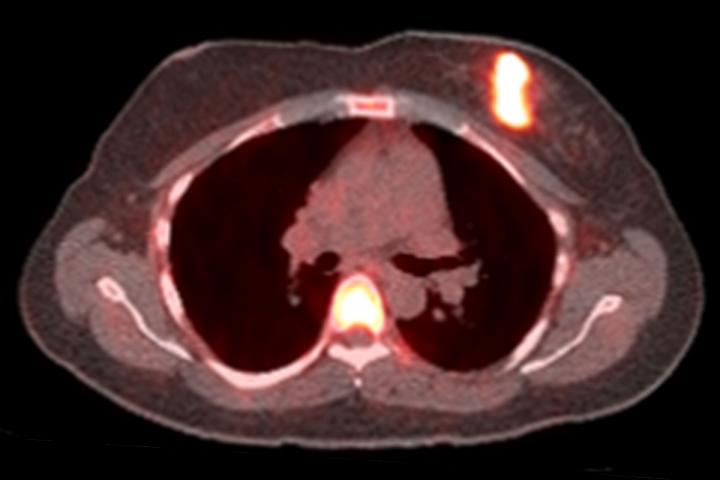

18F-fluciclovine PET/MRI can improve treatment guidance with better staging and evaluation of androgen deprivation therapy.